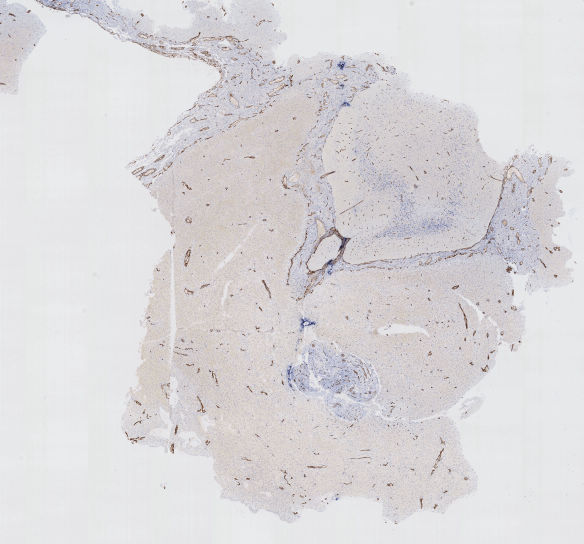

A detail from an example of such a mask of sharp tissue is shown, superimposed onto the corresponding WSI, in Figure 2.

Figure 2 - Example of a determination of tissue without blur.

Top left: excerpt of the original image (one of our WSI). Top right: the mask (logical and combination of the mask of tissue and of the mask of sharp regions) is superimposed onto the WSI. Only regions considered, after our method, as sharp tissue are shaded. One can see in particular that tears inside the tissue are properly not counted as tissue (some of them are marked ‘T’). Blurred regions (some of them are marked ’B’) tend to form three vertical bands because of the way the image was acquired by the scanner. They will be excluded from the quantification process. Orange scale bar = 1 mm. Bottom left: detail of the top right image at the boundary of a blurred region. Bottom right: the mask of sharp regions is superimposed onto the detail of the WSI shown on the bottom left. One sees the transition between “fully blurred”, on the left-hand side of the image, to “fully sharp”, on the right-hand side of the image. Green scale bar = 20 microns.